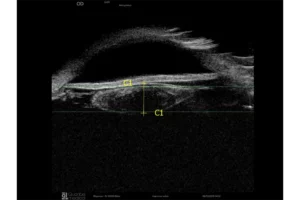

De sondes B15, B20-5A en UBM zijn uitgerust met een IMUv®-bewegingssensor die essentiële real-time informatie biedt, zoals:

- De positie van de sonde op het oog

- De visualisatie van het waargenomen gebied

Dit helpt de operator om onderzoeksgebieden eenvoudiger en sneller te identificeren. Deze technologie is gepatenteerd en exclusief voor Quantel Medical.